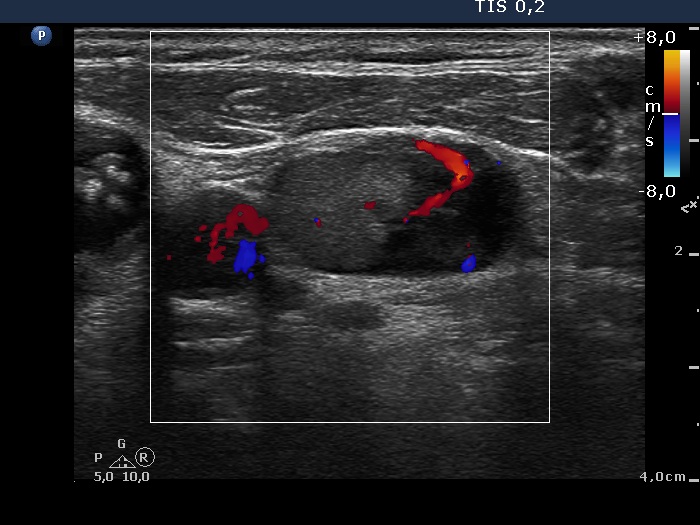

Right lobe, longitudinal scan

Left side of the neck, transverse scan, color Doppler mode. There is a large vessel within the lymph node.